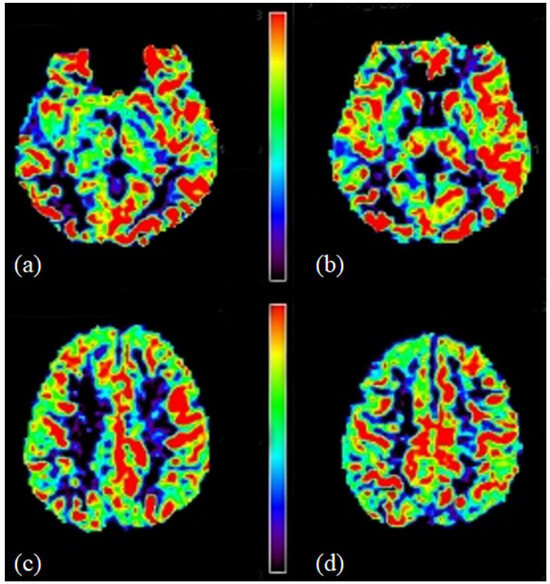

The head and neck and oral maxillofacial regions are composed of complex anatomical structures and contain various types of tissues. Radiological examination is one of the most important and widely used clinical approaches for understanding these regions. Advances in medical imaging acquisition and imaging analysis, including artificial intelligence, allow researchers and clinicians to understand the underlying physiology and pathology of these regions. These advances also offer the potential to integrate research findings to clinical practice.